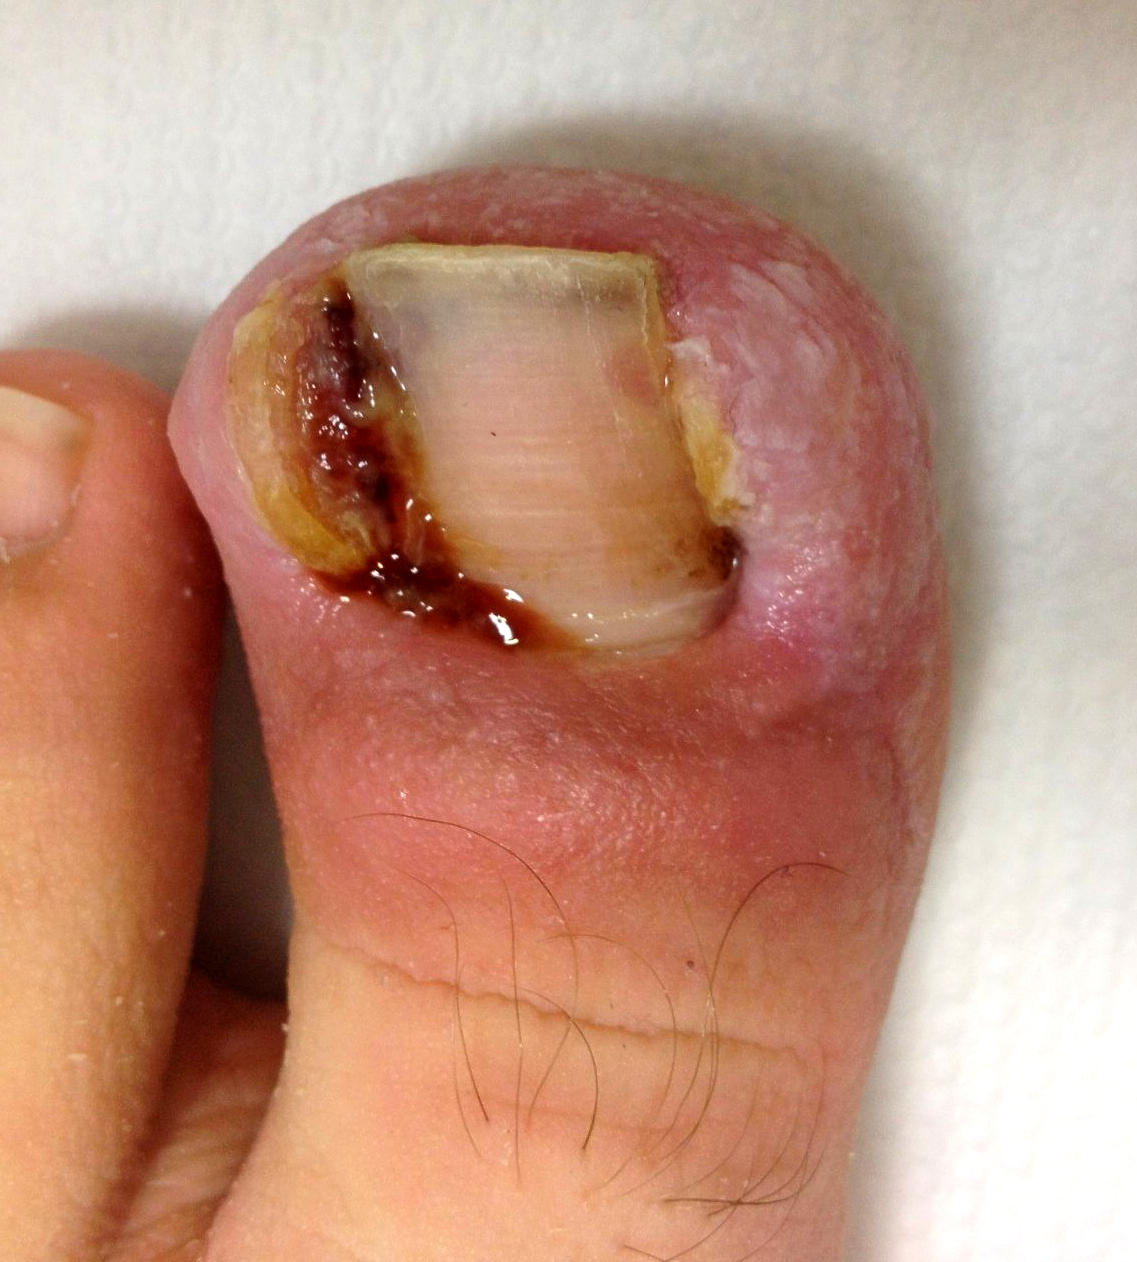

1.) Akutfall am Nagel

👉 Im Folgenden ein Akutfall der besonderen Art:

Kommt nicht sehr oft aber doch immer wieder einmal vor.

🔴 Der Nagelspan kommt bereits DURCH das Weichgewebe.

In Vergrößerung am Monitor auf Bild 2